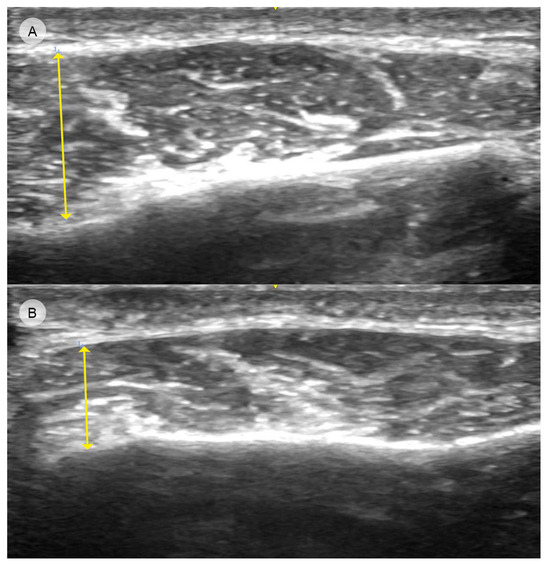

5.1. Paradoxical Bulging of the Masseter